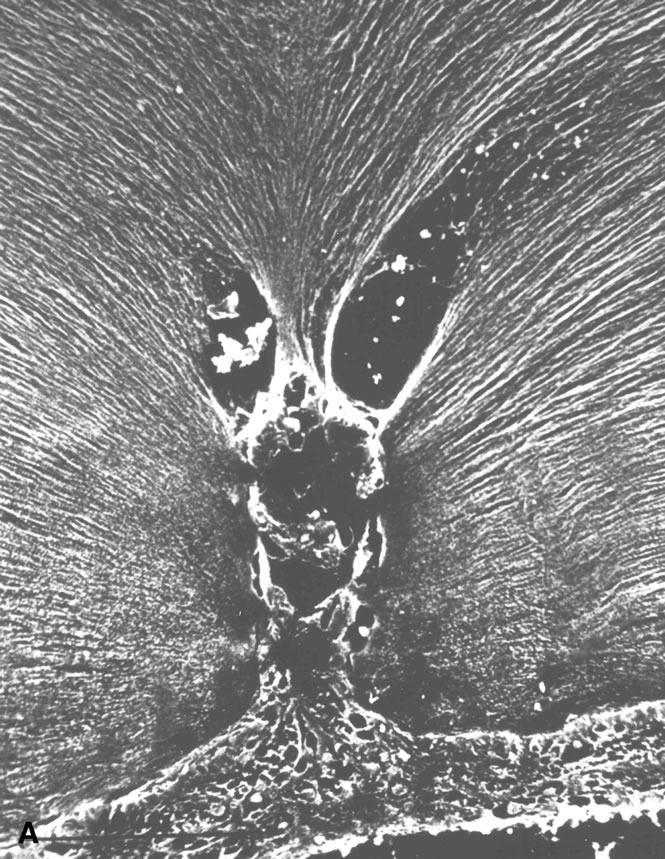

Persistent hyperplastic primary vitreous (PHPV) was first described by Reese28 as a congenital malformation of the anterior portion of the primary vitreous appearing as a plaque of retrolental fibrovascular connective tissue. This tissue is adherent to the posterior lens capsule and extends laterally to attach to the ciliary processes, which are elongated and displaced centrally. Although 90% of cases are unilateral, many of the fellow eyes have Mittendorf's dot or other anomaly of anterior vitreous development.29 A persistent hyaloid artery, often still perfused with blood, arises from the posterior aspect of the retrolental plaque in the affected eye. In severe forms, there is microphthalmos with anterior displacement of the lens-iris diaphragm, shallowing of the anterior chamber, and secondary glaucoma. PHPV is believed to arise from abnormal regression and hyperplasia of the primary vitreous.28 Experimental data suggest that the abnormality begins at the 17-mm stage of embryonic development.30 The hyperplastic features result from generalized hyperplasia of retinal astrocytes and a separate component of glial hyperplasia arising from the optic nerve head.31 The fibrous component of the PHPV membrane is presumably synthesized by these astrocytes and glial cells.32 A recent case report with clinicopathologic correlation found that collagen fibrils in this fibrous tissue had diameters of 40 to 50 nm with a cross-striation periodicity of 65 nm. The investigators concluded that the collagen fibrils differed from those of the primary vitreous and suggested that they arose either from a different population of cells or were the result of abnormal metabolism by the same cells that synthesize vitreous collagen.33

The retina is usually not involved in anterior PHPV. Indeed, previous studies have suggested that the anterior form is due to a primary defect in lens development and that vitreous changes are all secondary.34 This postulate has never been substantiated. There are rare instances of posterior PHPV in which opaque connective tissue arises from Bergmeister's papilla and persistent hyaloid vessels (Fig. 1).32,35 These can cause congenital falciform folds of the retina and, if severe, can cause tentlike retinal folds, leading on rare occasions to tractional and/or rhegmatogenous retinal detachment. Font and investigators36 demonstrated the presence of adipose tissue, smooth muscle, and cartilage within the retrolental plaque and suggested that PHPV arises from metaplasia of mesenchymal elements in the primary vitreous.